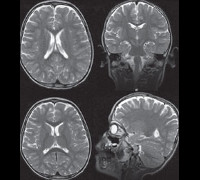

F84.2 Синдром Ретта